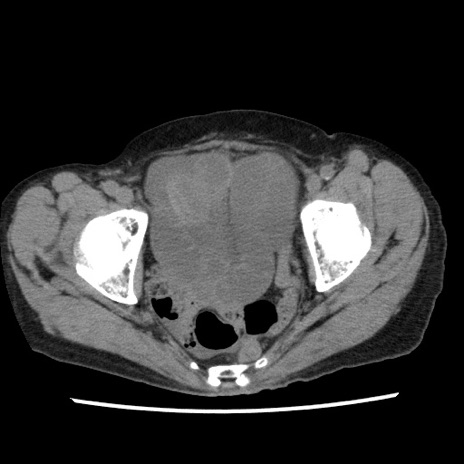

【症例】80歳代女性

【主訴】腹痛

【現病歴】8時間前から腹痛あり来院。

【既往歴】糖尿病、脂質異常症、子宮体癌にて子宮全摘術

【身体所見】意識清明・会話良好だが腹痛で苦悶様、全腹部にわたって反跳痛と圧痛あり

【データ】WBC 13600、CRP 0.14、LDH 224、CK 90